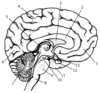

Pharynx

95

What is shown?

Lower Respiratory Tract & Larynx

96

Rib 4

97

Middle Lobe

98

Right Lower Lobe

99

Diaphragm

100

Left Lower Lobe

101

Trachea

102

Primary Bronchus

103

Larynx

104

Left Upper Lobe

105

Right Upper Lobe

106

Thyroid Cartilage

107

Thyrohyoid Membrane

108

Cricothyroid Membrane

109

Superior Thyroid Notch

110

Trachea

111

Cricoid Cartilage

112

Carina